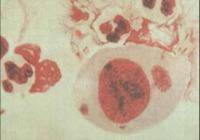

衣原體:直徑只有O.3-0.5um,多呈球狀、堆狀,有近似的細胞壁結構,含DNA、RNA及核蛋白體。衣原體有兩種存在形態,分別稱為原體和始體。原體有感染力,它是一種不能運動的球狀細胞。原體逐漸伸長,形成無感染力的個體,稱為始體,這是一種薄壁的球狀細胞,形體較大。

衣原體的發育周期分為原體和始體兩個階段。原體具有傳染性,可在宿主細胞外存活,始體僅存在於細胞內無傳染性。能引起人類非淋菌性尿道炎的主要有沙眼衣原體。